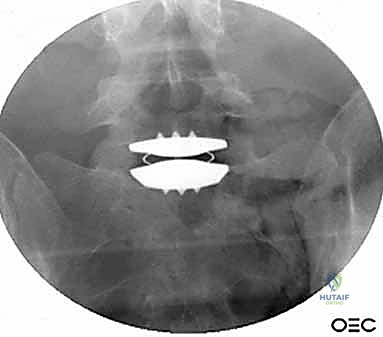

الخطوة 4: التحضير وزراعة القفص (Implant Insertion)

يتم قياس الفراغ المتبقي بدقة لاختيار الحجم المثالي للقفص الجراحي (Cage). يُصنع هذا القفص عادة من مادة PEEK أو التيتانيوم، ويتم حشوه بمادة عظمية (طعم عظمي ذاتي من المريض، أو طعم صناعي، أو بروتينات محفزة لنمو العظم BMP). يتم إدخال القفص بقوة في الفراغ، مما يؤدي فوراً إلى استعادة ارتفاع القرص الطبيعي وتوسيع المخارج العصبية (تخفيف الضغط غير المباشر).

الخطوة 5: التثبيت (Fixation)

لضمان أقصى درجات الثبات والسماح للعظم بالاندماج بمرور الوقت، يتم تثبيت القفص باستخدام شريحة معدنية صغيرة ومسامير من التيتانيوم تُثبت في الأجسام الفقرية من الأمام. في بعض الحالات، قد يرى الدكتور هطيف ضرورة إضافة تثبيت خلفي بمسامير عبر الجلد (Percutaneous Pedicle Screws) لزيادة الدعم.